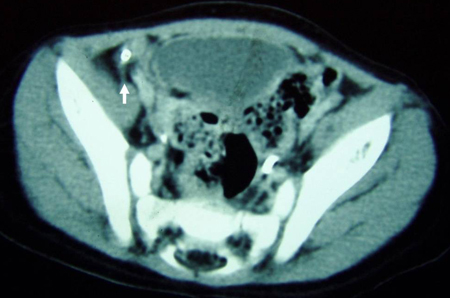

- tomografia computadorizada (TC) de abdome e pelve:

lesão em alvo: massa intraluminal de tecido mole, com uma área de gordura excentricamente posicionada; massa reniforme: alta atenuação periférica e atenuação central mais baixa; massa em forma de salsicha: áreas alternadas de baixa e alta atenuação representando a parede intestinal menos espaçada, gordura mesentérica e/ou fluido e gás intestinal

pode mostrar intussuscepção, divertículo de Meckel e/ou intestino dilatado consistente com obstrução intestinal

Mais - tomografia computadorizada (TC) de abdome e pelve:

lesões descontínuas e segmentares (skip lesions), espessamento da parede intestinal, inflamação adjacente, abscesso, fístulas

Mais - tomografia computadorizada abdominal:

intestino delgado dilatado; pode revelar uma zona de transição de obstrução, massa, tumor, abscesso

- tomografia computadorizada abdominal:

obstrução intestinal com padrão de turbilhão do mesentério

distensão gasosa do intestino grosso; pode revelar uma zona de transição de obstrução